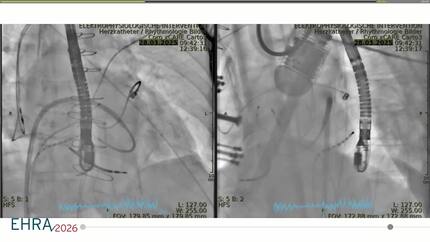

Successful catheter ablation of electrical storm with the lattice tip catheter in a patient with a left ventricular apical thrombus using echocardiographic guidance